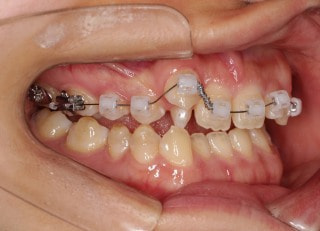

治療開始時

治療開始から25ヶ月後